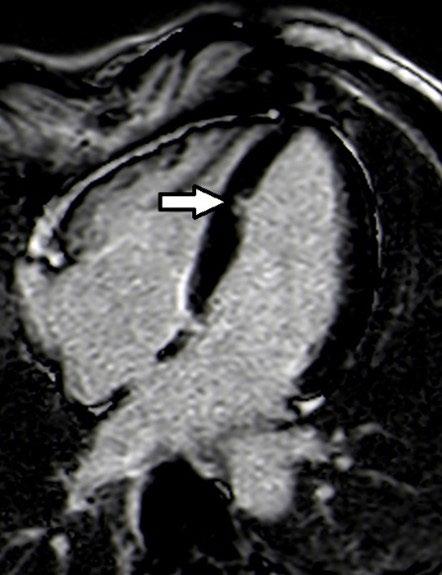

Create a flipbook